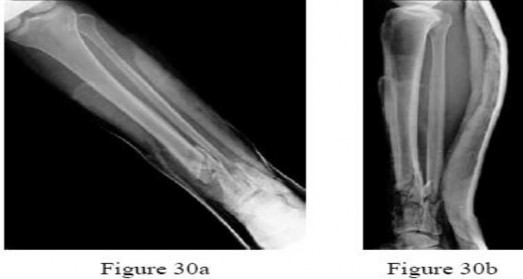

Figures 30a and 30b are the radiographs of a 61-year-old man with diabetes who fell from a ladder and sustained an isolated closed fracture. After realignment and splint application, what is the most appropriate next step in management?